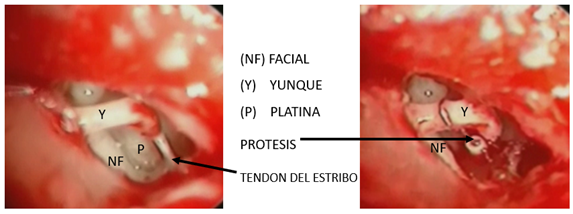

Figura 13. Maleoestapedotomía |

Figura 14. |

Presente en el 0,6 al 6% de los pacientes. Cuando se presenta, se realiza una resección de la cabeza y se aplica una prótesis que va desde el mango del martillo a la platina, lo que se le conoce como maleoestapedectomía (Fig.12-13).

La técnica clásica de estapedectomía consiste en una vez visualizado el estribo, el yunque, la apófisis piramidal, la ventana oval y redonda; cortar el tendón del estribo, retirar la superestructura del estribo, realizar la fenestración y, finalmente, colocar la prótesis.

Técnica Clásica